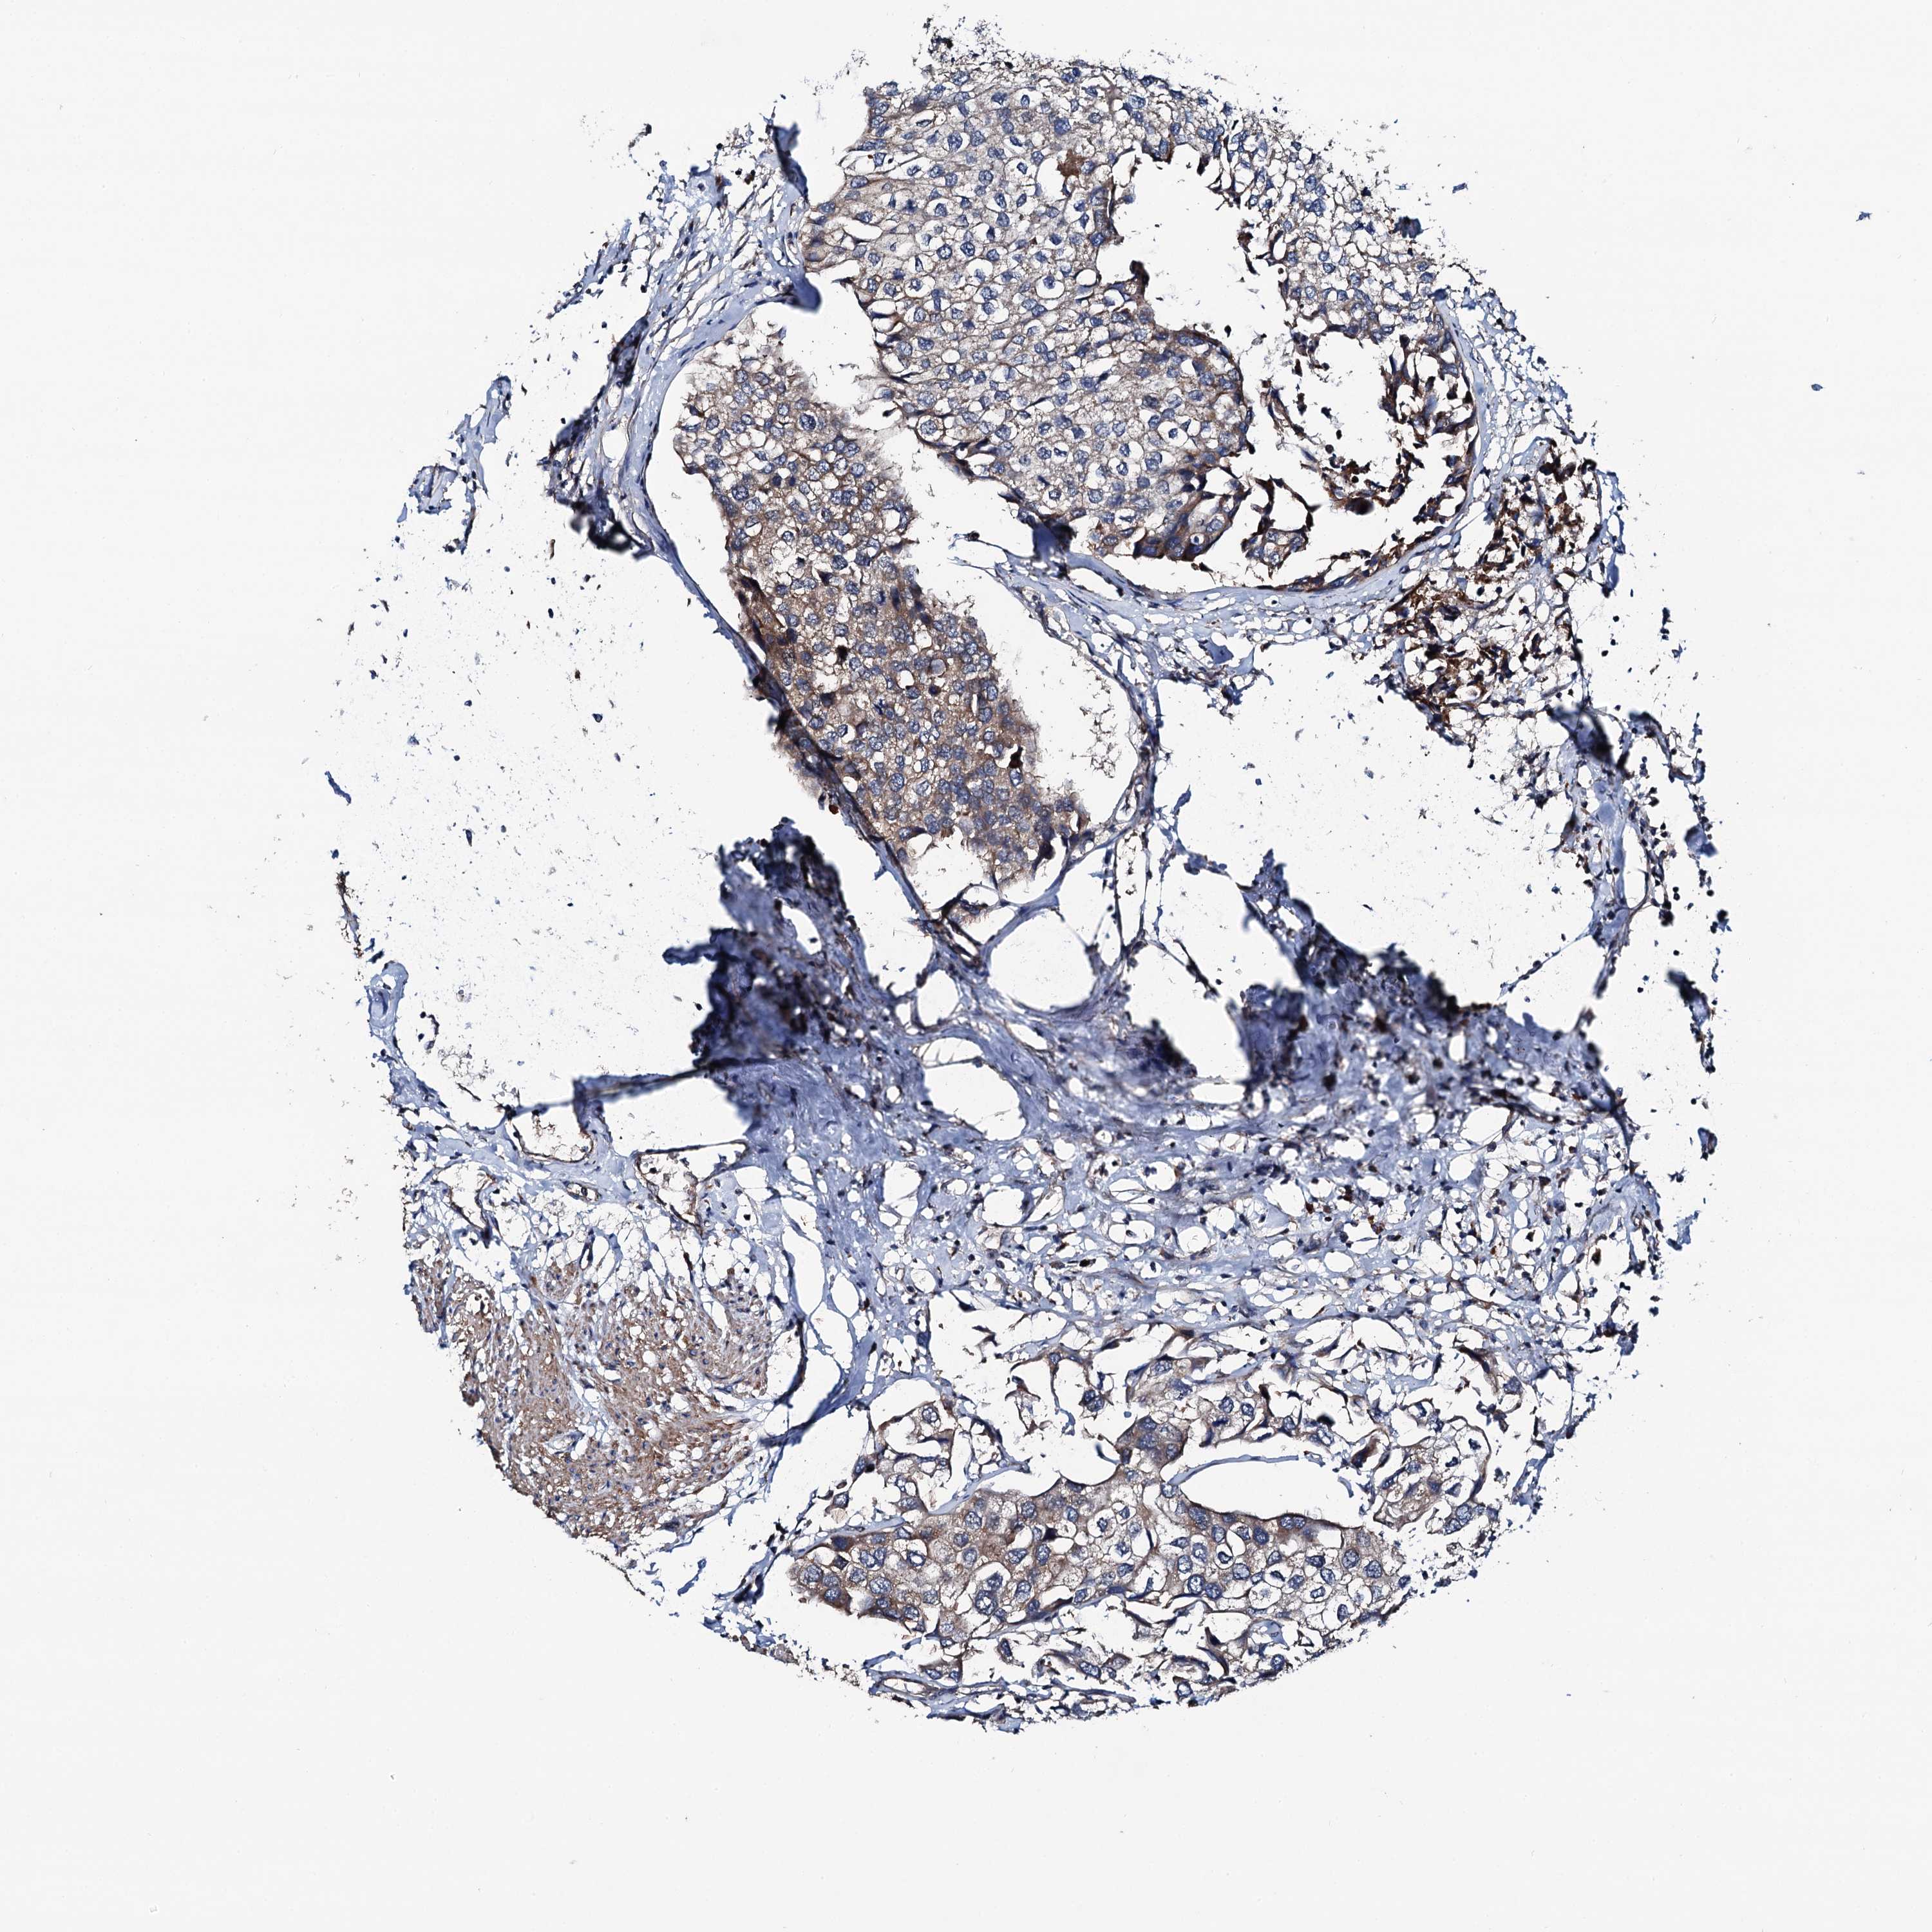

UROTHELIAL CANCER - Protein expressioni

A mouse-over function shows sample information and annotation data. Click on an image to view it in a full screen mode. Samples can be filtered based on level of antibody staining by selecting one or several of the following categories: high, medium, low and not detected. The assay and annotation is described here.

Note that samples used for immunohistochemistry by the Human Protein Atlas do not correspond to samples in the TCGA dataset.

Antibody stainingi

Antibody staining in the annotated cell types in the current human tissue is reported as not detected, low, medium, or high, based on conventional immunohistochemistry profiling in selected tissues. This score is based on the combination of the staining intensity and fraction of stained cells.

Each image is clickable and will lead to virtual microscopy that enables deeper exploration of all samples and also displays staining intensity scores, fraction scores and subcellular localization as well as patient and tissue information for each sample.

Antibody HPA020873

Antibody HPA040413

Urothelial carcinoma, High grade

Urothelial carcinoma, Low grade

Urothelial carcinoma, NOS